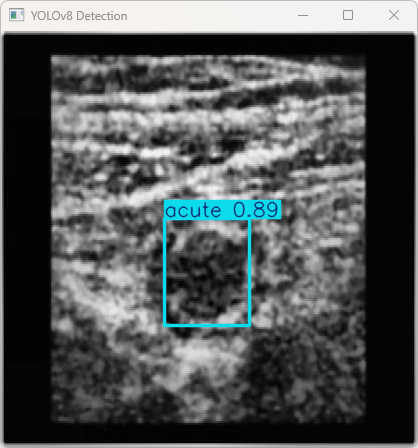

执行imgTest.py代码后,会将执行的结果直接标注在图片上,结果如下:

该段信息基于YOLOv8模型对图像imagetest.jpg进行检测所得的结果表明

图像信息:

(1)处理的图像路径为:TestFiles/imagetest.jpg。

(2)图像尺寸为640×640像素。

检测结果:检测到1个目标:acute (急性阑尾炎的病变)

处理速度:

(1)预处理时间: 4.0 毫秒

(2)推理时间: 5.2 毫秒

(3)后处理时间: 78.1 毫秒